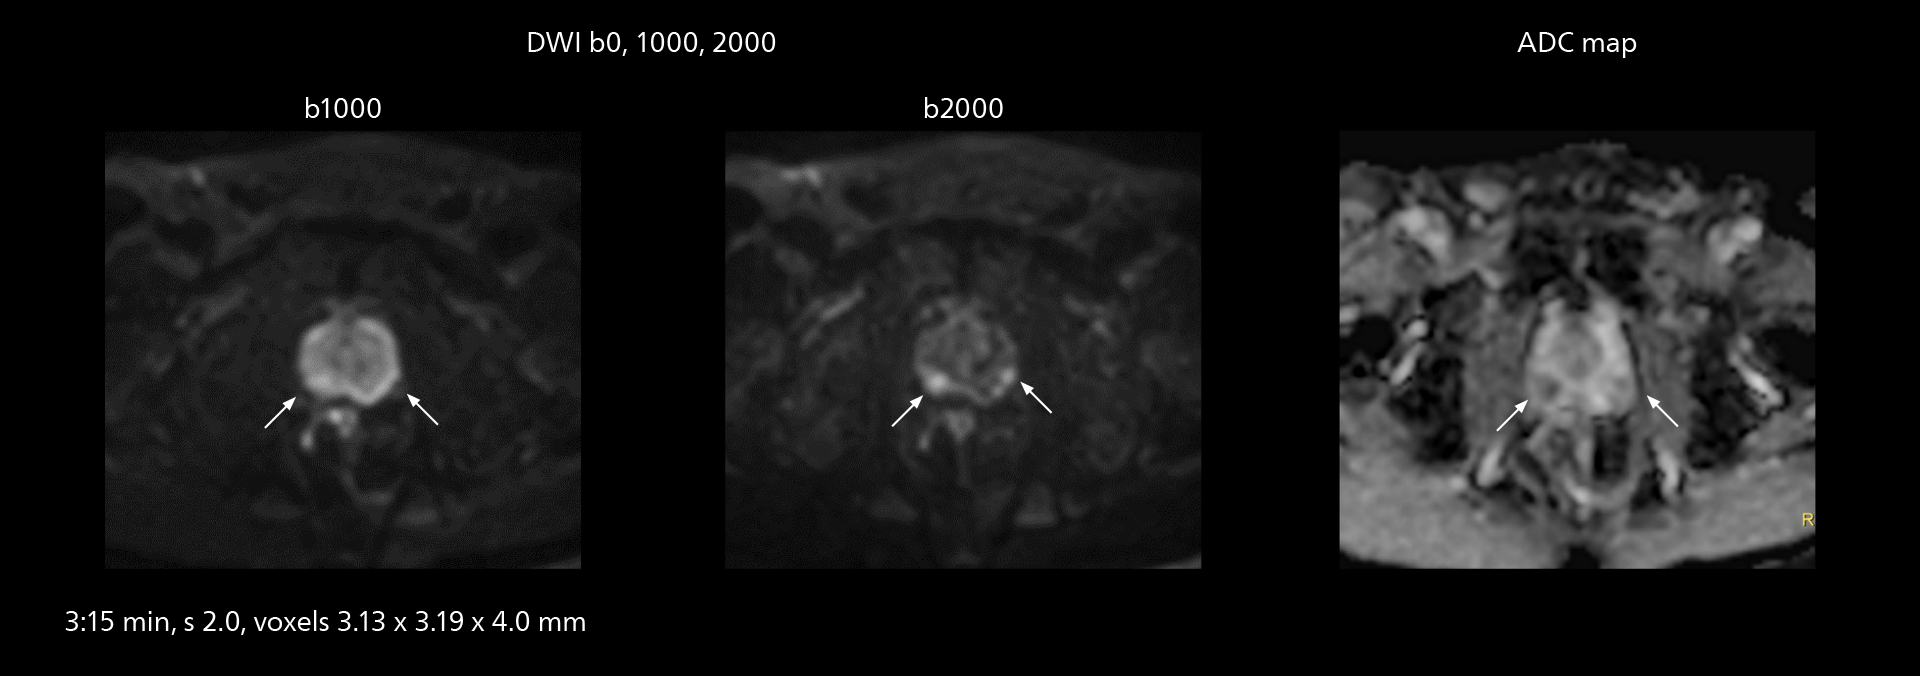

The value of the Elition X gradients is also evident in DWIBS studies. “The fact that we can consistently obtain distortion‐free DWIBS while reducing imaging time at three coronal stations is excellent,” Dr. Makuuchi says. “In these patients, it’s also important that the application of Compressed SENSE to T2‐weighted, STIR and mDIXON sequences has no impact on the examination time of whole‐body imaging. As a result of the increased speed and higher image quality we realize, DWIBS studies have now become routine examinations.”

With SmartPath to Elition X the team can obtain excellent quality DWIBS imaging and reduce imaging time. Other sequences also fit in the examination slot. This case shows left paravertebral neurogenic tumor and Th10 vertebral hemangiomas.